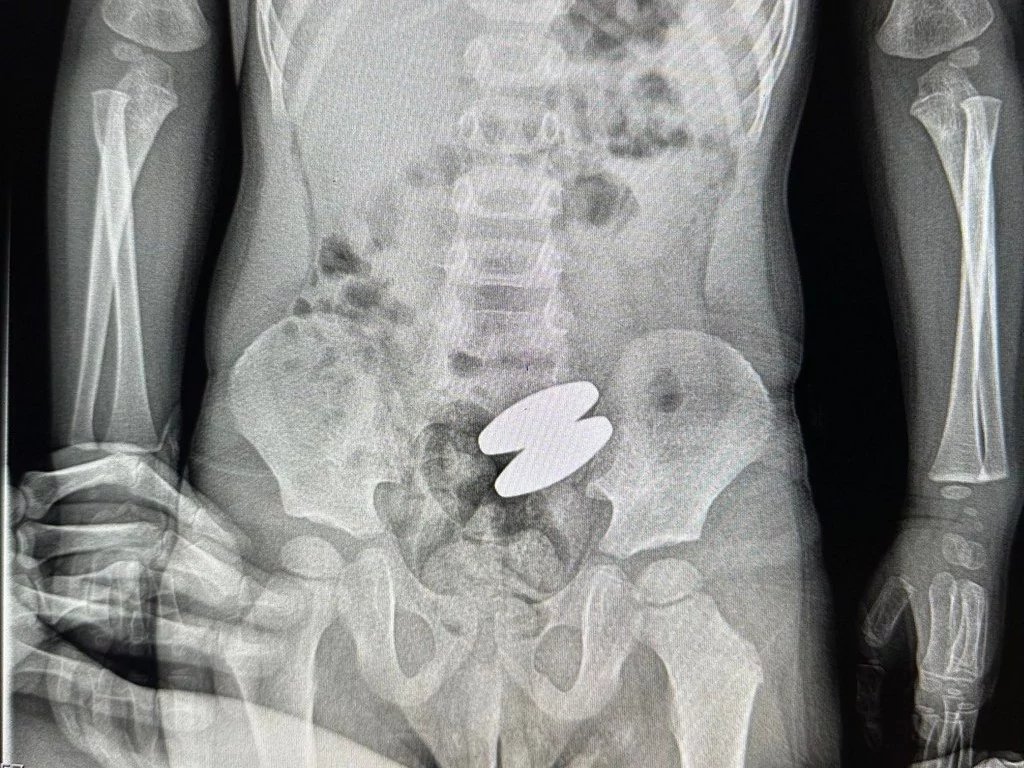

Два магніти досить великого розміру лікарі у Луцьку вилучили із кишківника 2-річного хлопчика. Як розповіла мама малюка, магніти він зняв із холодильника — ними прикріплювали записки, календарі. Про це повідомили на фейсбук-сторінці Волинського обласного медоб'єднання захисту материнства і дитинства. В неділю, 27-го ...